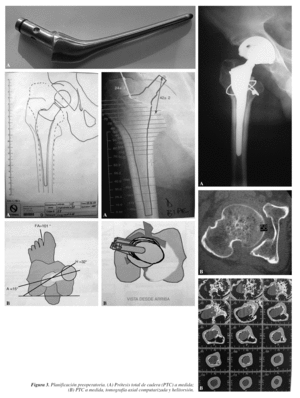

Son las primeras que hay que tener en cuenta y consisten en realizar una correcta planificación con las plantillas (figs. 2 y 3), con el fin de reproducir el acodo lo más exactamente posible, el centro de rotación de la cadera y la longitud del miembro9-12. Los pasos conocidos, pero que conviene recordar, son los siguientes:

1. Anteroposterior de pelvis con el foco en la sínfisis pubis.

2. Anteroposterior de la cadera a intervenir y que se vea 20 cm de fémur.

3. Proyección lateral o axial.

1. Datos del paciente, diagnóstico, lado a intervenir y tipo de implante.

2. Sobre la radiografía anteroposterior (Rx AP) de pelvis se traza una línea horizontal que una ambas tuberosidades isquiáticas, comprobando que comprende ambas corticales femorales.

3. Marcar en la misma Rx el punto más proximal de ambos trocánteres menores.

4. Medir la distancia desde el punto proximal del trocánter menor a la línea biisquiática. Cuanto mayor sea la distancia más corta estará la pierna. Si se presenta esta situación hay que anotar la diferencia de longitud de los miembros inferiores.

5. Sobre la radiografía anteroposterior de la cadera se determina el tamaño apropiado, la posición y componente acetabular con las plantillas; después se marca el centro de rotación de la cadera.

Desde el punto de vista práctico, una planificación quirúrgica sería:

1. Nombre, apellidos y número de historia.

2. Edad y sexo.

3. Diagnóstico, tipo de implante cementado (sí/no, mixto).

4. Diferencia, si existe, de longitud de los miembros inferiores (MMII).

5. Cotilo: diámetro en mm, hemisférico, monobloque, perforado, insertos polietileno, cerámica, metal, tamaño interior.

6. Vástago: offset, número, si está cementado o no.

7. Corte del cuello a xx mm por encima del trocánter menor.

8. Longitud del cuello de más de 3,5 mm de diámetro; cabeza en mm metálica/cerámica.

9. Con esta reconstrucción se alarga o no el miembro.

10. Equipo especial que se puede necesitar: a) cotilos y fresas más pequeñas de lo habitual; b) cabezas de 26 mm de diámetro si hubiese que utilizar cotilos pequeños; c) cables de Dall-Miles o material de osteosíntesis en caso de fractura; d) instrumental específico para extraer implante; cortar cerámica, etc.